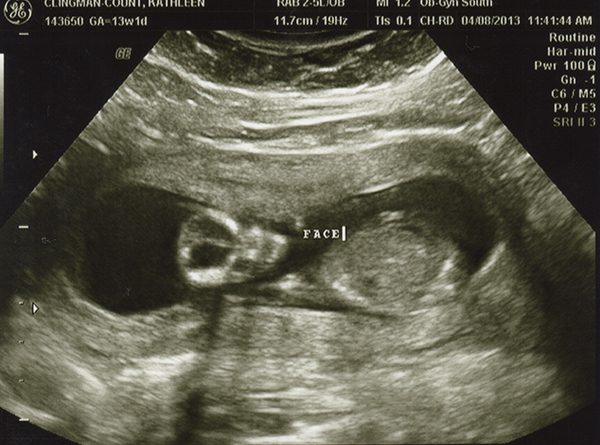

I had an ultrasound on Monday -- 13 weeks. I don't feel as though any of these are very clear pics. Even if they were better, I still wouldn't be any good with ultrasounds! Any of you experts able to make anything out with these? The tech guessed boy but the picture is not clear to me at all! She also kept saying the cord was between baby's legs and that we shouldn't go out and buy anything blue just yet. Any hope that it's a girl??

Attachment 10495